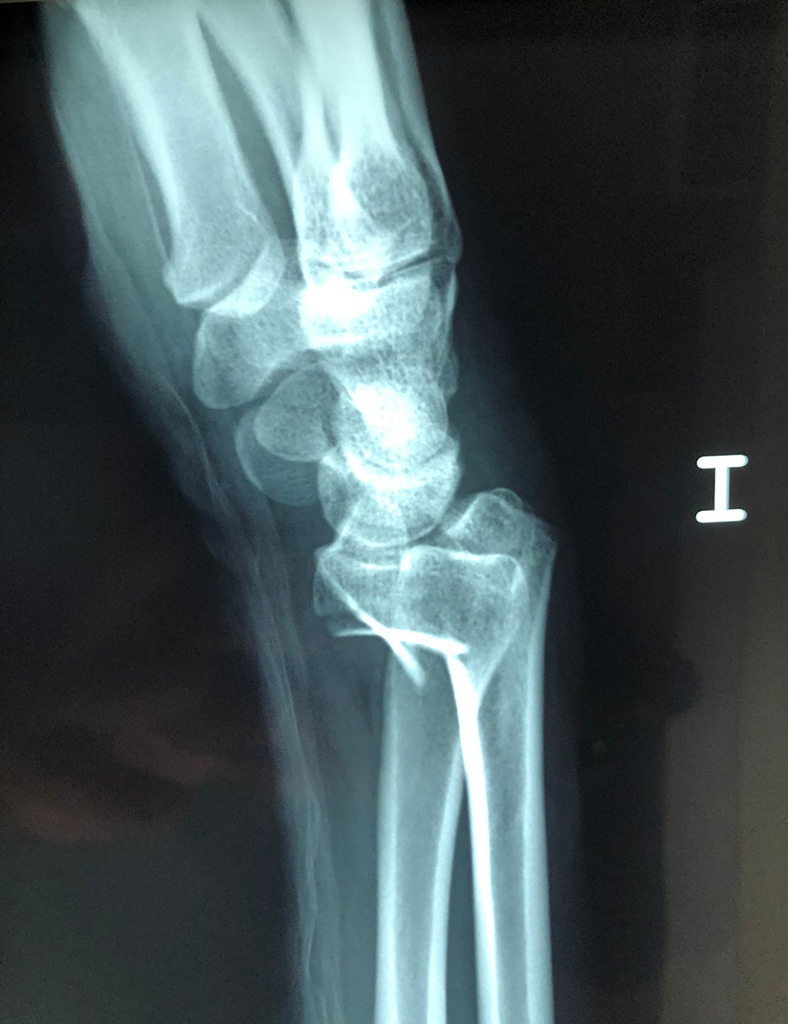

Cirugías de Codos - Cirugías de Muñecas y Manos

Los procedimientos más comunes en cirugía de la mano son aquellos destinados a reparar traumatismos, incluyendo lesiones de tendones, nervios, vasos sanguíneos, y articulaciones; huesos fracturados; y quemaduras, cortes, y otros daños de la piel.